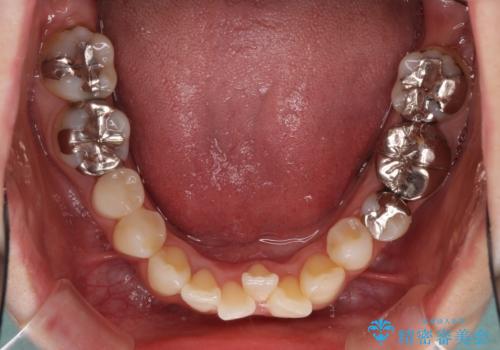

- 上下のデコボコと奥歯の咬みにくさを気にして来院された患者様です。

上顎骨の幅が下顎骨よりも小さいので、拡大装置により骨幅を広げて上下関係を改善し、その後インビザラインにて歯並びを整えることとしました。

上下の骨幅を改善したことで、スムーズに歯列矯正を行うことができました。

矯正治療中に近医で銀歯を外す治療を開始したため、治療後に奥歯の咬み合わせが不十分ですが(こちらは近医での治療により改善するとのこと)、歯列と咬み合わせが改善され、患者様には大変満足していただきました。